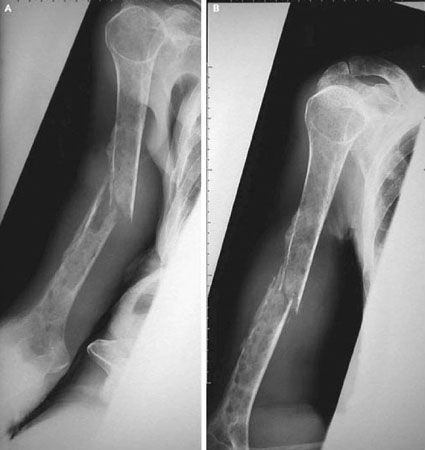

Mise au point Prise en charge initiale des traumatismes médullaires , Frédéric Jacquot Pôle Appareil Locomoteur, Hôpital Saint Antoine, 184 rue du Faubourg Saint Antoine, 75012 Paris, France , G. Loubert Hôpital Raymond Poincaré - 92380 Garches - , T. Loeb Hôpital Raymond Poincaré - 92380 Garches - , F. Signoret Hôpital Raymond Poincaré - GARCHES , Jean-Marc Feron Hôpital Saint-Antoine, 75012 Paris, France N°102 - Mars 2001 ● 29 min de lecture